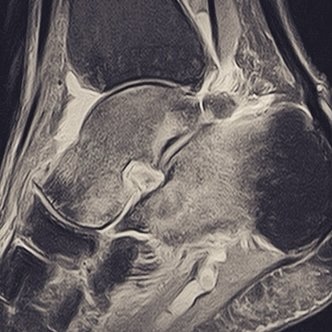

Tras unas 3 o cuatro semanas sin correr, decidí salir a trotar un par de kilómetros para ver si molestaba, dolía o simplemente, corría sin ningún problema. Ese par de kilómetros se convirtieron un unos miserables 800 metros, ya que el tobillo se quejó con un pinchazo que me hizo volver a casa a coger las llaves del coche para pasarme por urgencias. El diagnóstico fue de edema óseo y el tratamiento magnetoterapia y reposo.